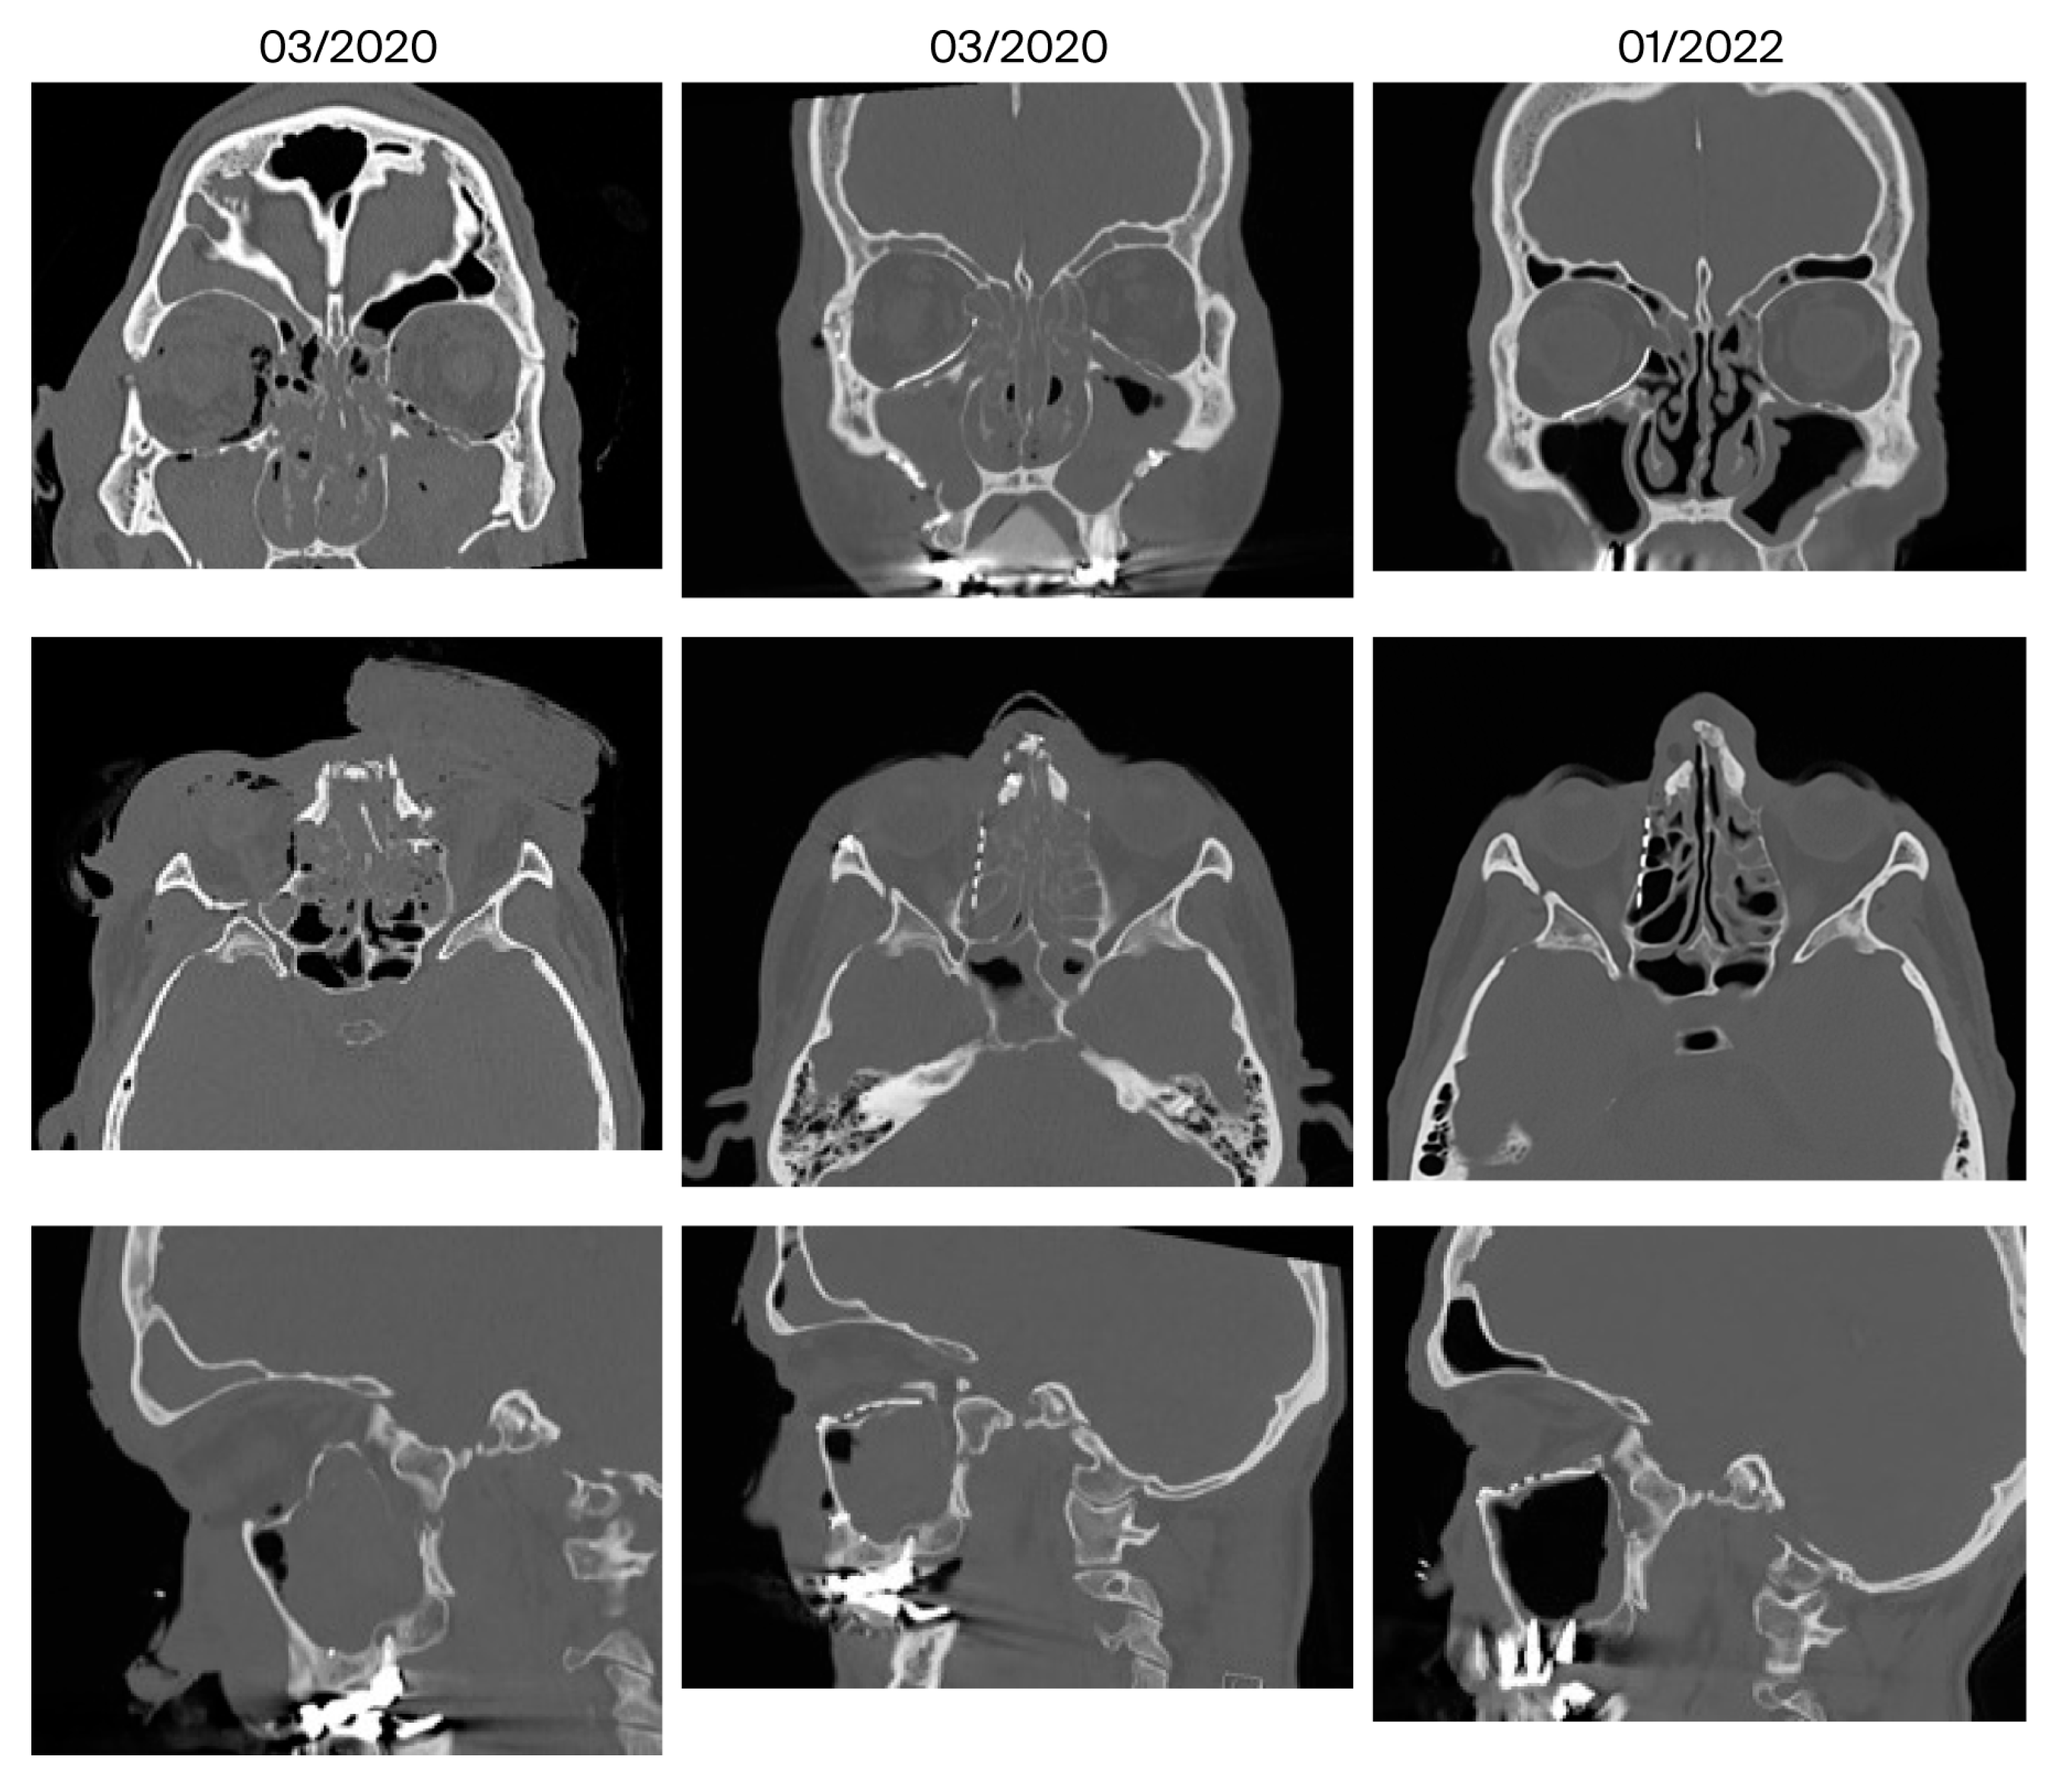

| 12 | February 2021 June 2022 (16 months) | Amaurosis, blepharophimosis, soft tissue deficit of the nasal wings; forehead flap planed | Yes, additionally neo-infundibulum | 2/1 | No | Minor, ethmoidal transition zone | Yes |